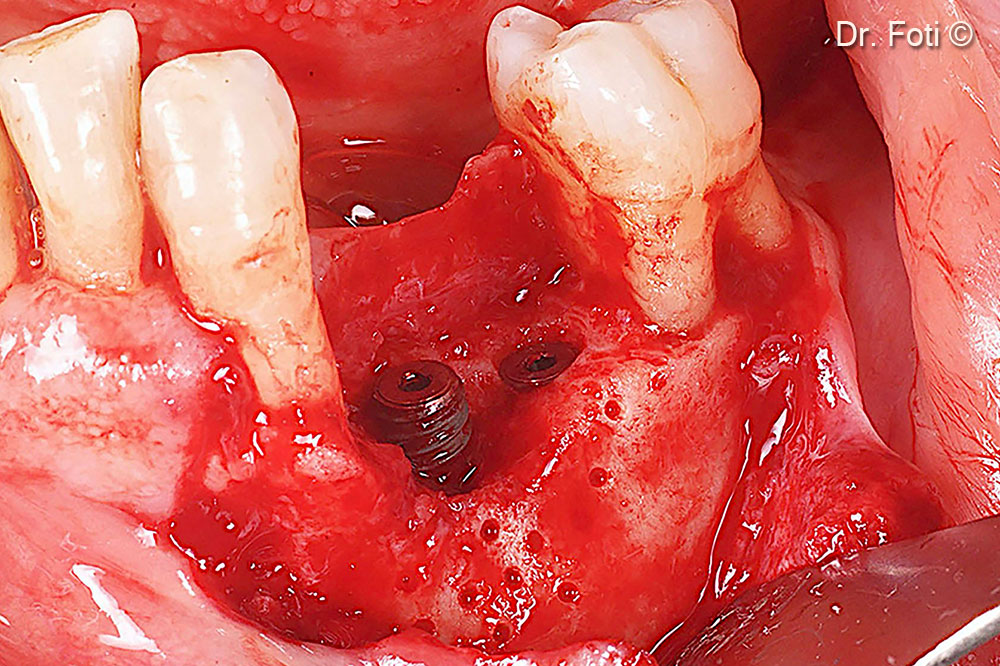

Two implants are placed. The cortical bone is drilled to promote bleeding and recruit Mesenchymal Stem Cells